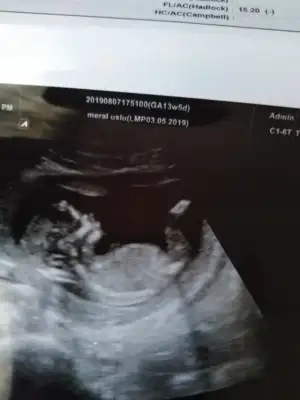

geçen haftaki usg ler.. 11+2

Erkek